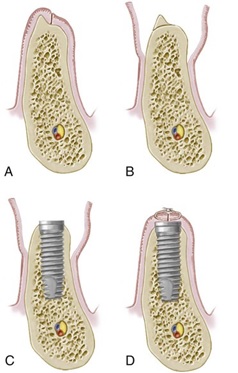

روش دو مرحله ای:

در این روش دو جلسه جراحی برای کاشت ایمپلنت وجود دارد. طی جلسه اول پایه ایمپلنت (فیکسچر) در استخوان کاشته میشود و لثه روی آن بخیه میشود.سپس جهت جوش خودن ایمپلنت ۲-۳ ماه فرصت داده میشود. در این روش ایمپلنت در زیر لثه و داخل استخوان مدفون است و بیمار پس از جراحی بجز برش و بخیه چیزی در دهانش نمیبیند. بعد از طی شدن این مدت جراحی جلسه دوم گذاشته میشود که بسیار جراحی ساده و راحتی است و طی آن روی ایمپلنت باز میشود و پیچی(healing abutment ) روی آن بسته میشود تا جهت قالب گیری آماده شود. این روش بیشتر در مواقعی که پیوند استخوان لازم است انجام میشود. هدف از جراحی دو مرحله ای جلوگیری از هر گونه فشار بر ایمپلنت است.